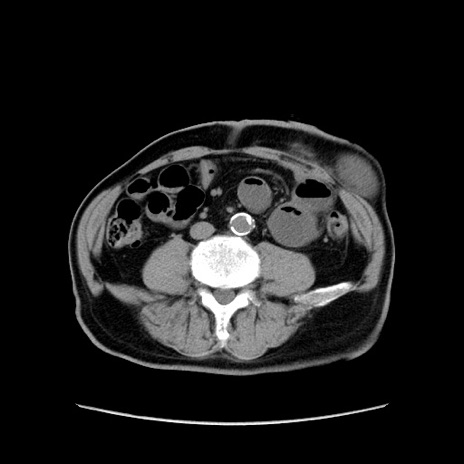

症例24(横断像)

【症例】80歳代男性

【主訴】左側腹部痛、嘔吐

【現病歴】本日早朝より左腹部に痛みあり。昼頃嘔吐認めたため、救急要請。

【既往歴】直腸癌(Mile手術)、胆摘

【身体所見】意識清明、BT 35.9℃、BP 221/93mmHg、SpO2 97%(RA) 、腹部:左ストーマ周囲に限局性の腹部膨隆あり。 膨隆部自発痛・圧痛あり・軟。

【データ】WBC 7700、CRP 0.09